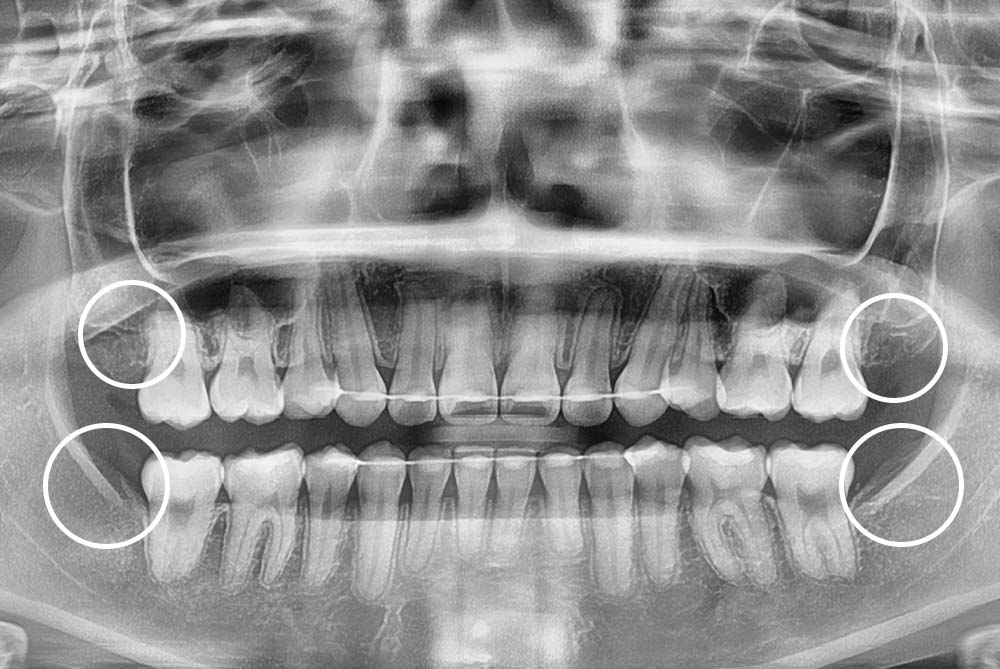

[사랑니] 매복 사랑니 발치

치료전 : 2018-11-26